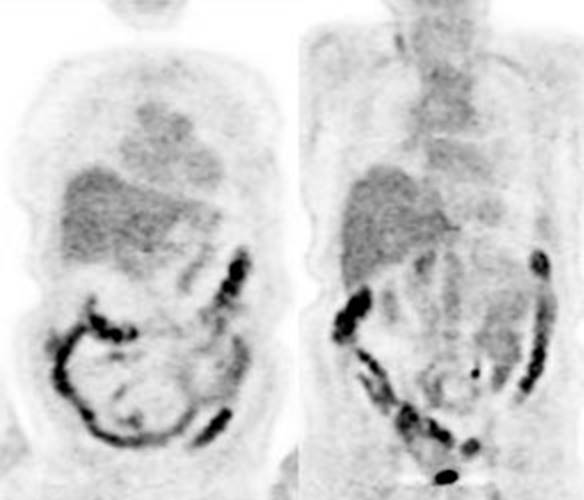

Figure 13 - Normal

bowel activity: Faint

heterogeneous bowel uptake is common

Figure 14 - Intense right colon

activity: Note the

intense activity in the right colon in this asymptomatic patient. Increased

activity in the right colon can sometimes be seen. Note uptake in the patients

left upper lobe lung cancer. Focal activity in the left upper abdomen was

related to the stomach

Figure 15 - Diffuse large bowel

activity: Diffuse

increased colonic FDG uptake was seen in this asymptomatic patient. Diffuse

uptake is usually not associated with underlying bowel abnormality.

Figure 16 - Focal colonic uptake

associated with colon cancer: This patient had focal tracer uptake in the region of the cecum. CT

demonstrated a soft tissue mass which was found to be a primary colon cancer on

colonoscopy. Focal areas of colonic tracer uptake should be further evaluated.

Figure 17 - Segmental colon activity in

diverticular disease:

Note the segmental FDG uptake corresponding to an area of severe diverticular

disease on CT. There is likely underlying inflammation or muscular spasm which

contributes to the FDG uptake